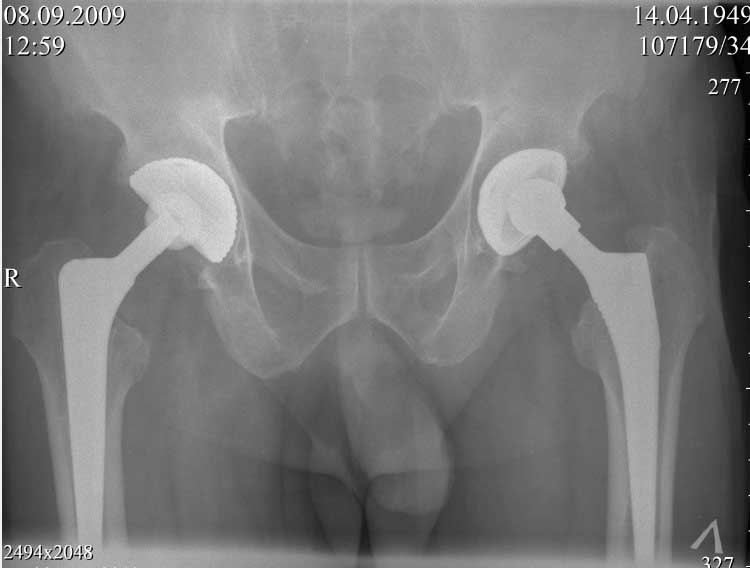

ниже снимок в 2008 году

далее снимок в 2009 году

далее снимок у меня на приеме

Пациент 60 лет, мужчина. Оперирован в 2007 году, поочередно оперированы два тазобедренных сустава с интервалом в 4 месяца. В 2008 году оперирован на сердце(аорто-коронарное шунтирование).Операция осложнилась инфицированием операционной раны в области грудины, лечился в гнойном отделении.

В конце 2008 года отметил боли в правой паховой области при опоре на правую ногу. На рентген снимках таза с тазобедренными суставами явных признаков нестабильности вертлужного компонента не обнаружено. В 2009 году нейрохирурги его "успешно" прооперировали на L\3-\4 связывая болевой синдром в правой паховой области с наличием грыжи указанного межпозвонкового диска. Состояние только ухудшилось, больной уже не мог долго сидеть, боль прогрессировала . Его в 2009 и 2010 годах смотрел ортопед, делались рентгенснимки, но почему то приходили к выводу что эндопротез справа стабилен. В марте 2011 года я впервые увидел его, через одну неделю после этого был прооперирован. На операции вертлужный компонент при упоре на него инструментом прокручивался во впадине и без труда был извлечен.

Эндопротез Ножка Cerafit компании Ceraver- чашка той же компании.

Расшорошили вертлужную впадину (дебридмент) Заменили чашку,учитывая невозможность полностью исключить инфекционный генез нестабильности, установили вертлужный компонент цементной фиксации (цемент с ванкомицином), поменяли головку из-за изменившихся взаимоотношении между бедренным компонентом и новой чашкой. Рану зашили наглухо. Провели антибактериальную терапию Кубицином. Выписали на 10 сутки после операции. Болевой синдром купирован, пациент радостный, уехал к себе в Калугу. Приедет на контрольный осмотр через месяц.